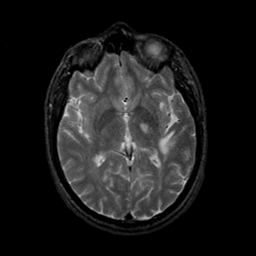

MR Study #9, April 14, 1991 -- Slice #25